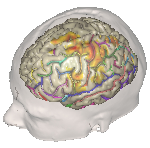

When Qt/QML is used for creating graphical user interfaces, the software documentation must include revision history for change control in the Qt development process. This should also include a description of user interface guidelines and performance tests characterizing the stability of Qt software on workstations and embedded platforms. The FDA has cleared the QNX OS for Medical 1.1 in conformance with IEC 62304 standards as a platform for medical device software development [3]. Various gesture controls and interoperability (IO) devices can be incorporated to improve the clinical interface adding to patient safety and improved surgical intervention. The illustrations below indicate the power of visualization applied to medical image reconstruction and display.

Image [A] BrainVISA HBM (Human Brain Mapping) Image [B] VTK.org Creative Commons

Figure 3. Examples of volumetric reconstruction using BrainVisa and VTK. [4, 5, 6]